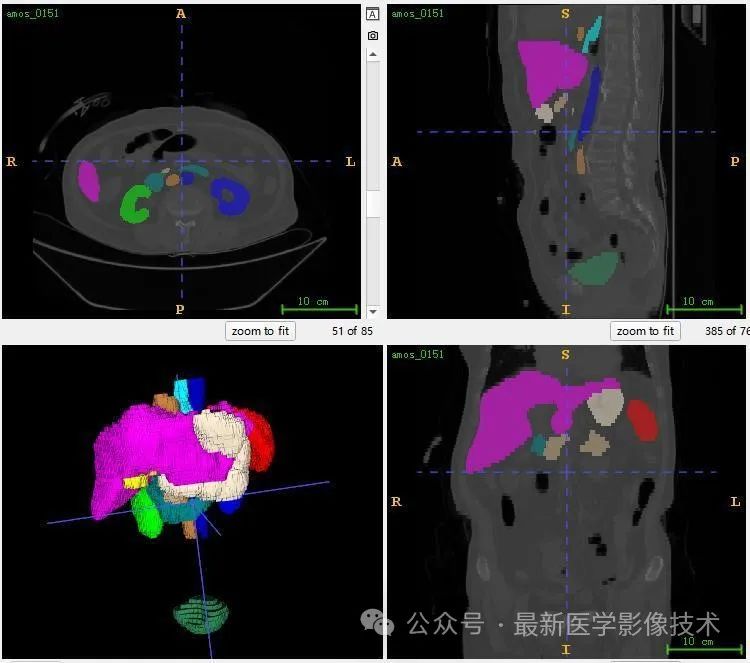

13、测试集分割结果

12、验证集分割结果

左图是金标准结果,右图是预测结果。